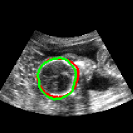

To quantitatively compare our network to the only other brain extraction method for fetal 3D US, the out test dataset was analysed with the method described in Namburete et al., 2018 [8]. The same experiments were performed and the results are shown in Table 3. Our network manages considerably better results throughout all comparisons. This is expected, since the other method relies on an approximation of the brain volume as ellipsoid, which does not accurately represent its shape. While an ellipsoid would be expected to have a high SC, its fitting to the probability mask results in an inaccurate alignment, which is reflected in the low SC of 0.74, compared to our network’s 0.95. This can be clearly seen in Fig. 7, where a comparison of their method with ours is shown.

| Original | Namb. 01 | Namb. 02 | Our work |